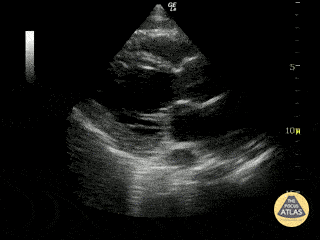

Left Ventricular Dysfunction - Severely Reduced EF